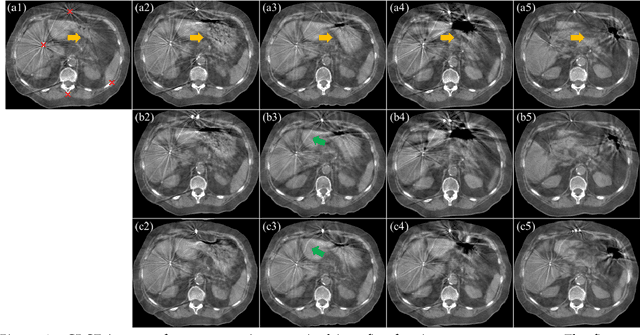

Abstract:CBCTs in image-guided radiotherapy provide crucial anatomy information for patient setup and plan evaluation. Longitudinal CBCT image registration could quantify the inter-fractional anatomic changes. The purpose of this study is to propose an unsupervised deep learning based CBCT-CBCT deformable image registration. The proposed deformable registration workflow consists of training and inference stages that share the same feed-forward path through a spatial transformation-based network (STN). The STN consists of a global generative adversarial network (GlobalGAN) and a local GAN (LocalGAN) to predict the coarse- and fine-scale motions, respectively. The network was trained by minimizing the image similarity loss and the deformable vector field (DVF) regularization loss without the supervision of ground truth DVFs. During the inference stage, patches of local DVF were predicted by the trained LocalGAN and fused to form a whole-image DVF. The local whole-image DVF was subsequently combined with the GlobalGAN generated DVF to obtain final DVF. The proposed method was evaluated using 100 fractional CBCTs from 20 abdominal cancer patients in the experiments and 105 fractional CBCTs from a cohort of 21 different abdominal cancer patients in a holdout test. Qualitatively, the registration results show great alignment between the deformed CBCT images and the target CBCT image. Quantitatively, the average target registration error (TRE) calculated on the fiducial markers and manually identified landmarks was 1.91+-1.11 mm. The average mean absolute error (MAE), normalized cross correlation (NCC) between the deformed CBCT and target CBCT were 33.42+-7.48 HU, 0.94+-0.04, respectively. This promising registration method could provide fast and accurate longitudinal CBCT alignment to facilitate inter-fractional anatomic changes analysis and prediction.